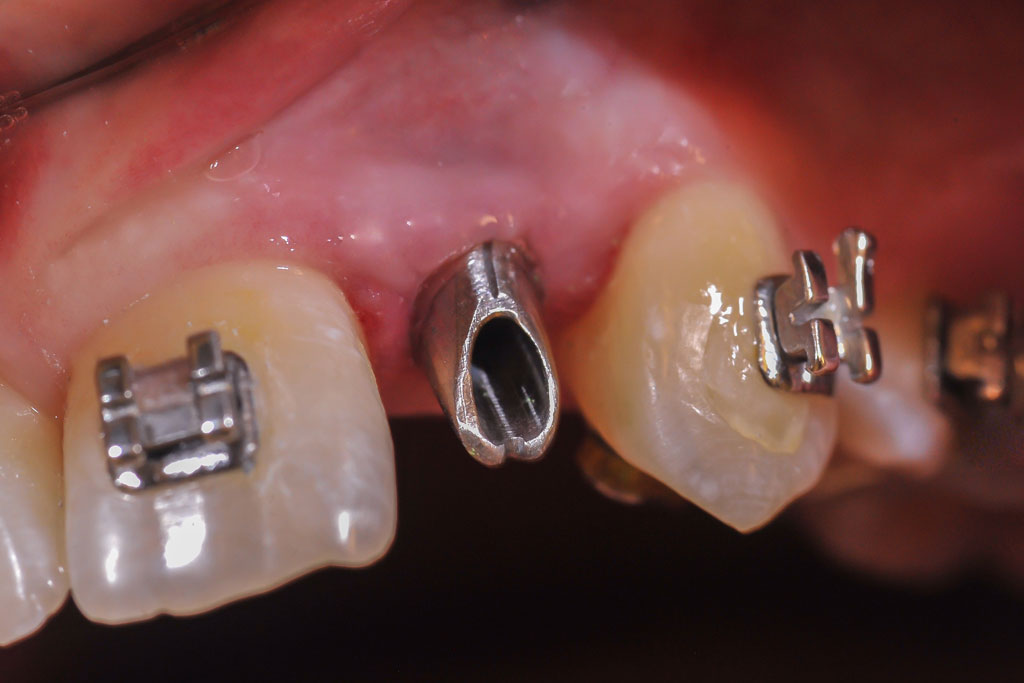

Die Nichtanlage der seitlichen oberen Schneidezähne und der zweiten unteren kleinen Backenzähne (Prämolaren) ist relativ häufig.

Wir verfügen über eine jahrzehntelange Erfahrung in der kieferorthopädischen Vorbehandlung, Implantologie und der prothetischen Versorgung von Nichtanlagen, sowie der Chirurgie und der Einordnung von verlagerten bleibenden Zähnen ohne den Einsatz von Implantaten.